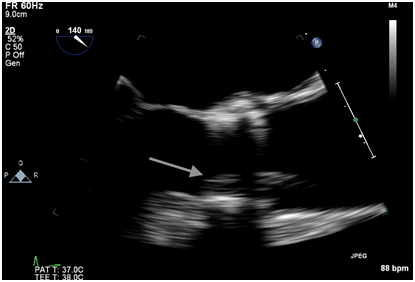

Figure 1A Intraoperative TEE post valve deployment showing the echodensity prolapsing across the valve prosthesis into the aorta.

Immediately after the prosthetic valve deployment, intraprocedural TEE revealed a 20 x 9.5 mm mobile echo density attached to the ventricular side of the strut along the right coronary cusp. The structure intermittently prolapsed through the leaflets of the newly placed valve prosthesis during systole (Figure 1A, 1B). However, only mild (1+) central aortic regurgitation was noted (Figure 2). There was no left ventricular outflow tract obstruction and the prosthetic valve leaflet excursion was otherwise normal. The peak and mean aortic valve gradients were 7 and 4 mm Hg respectively post deployment.

Figure 1B Intraoperative TEE post valve deployment showing an echodensity attached to the ventricular side of the strut along the right coronary cusp protruding into the left ventricular outflow tract.